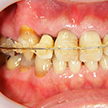

1. 初診時正面

この患者様の主訴は右下7番(第2大臼歯)の詰め物の脱離でした。口腔内写真を撮らせていただくと右上の八重歯(3番の唇側転移)が顕著でその叢生の結果、周囲が不潔となり歯肉炎およ2番(第2前歯)の歯頚部の異常他退縮が認められます。

5. 初診時右側

八重歯を中心とした叢生が顕著です。その周囲のみが既にクラウンとなっており、不適合が目立ちます。